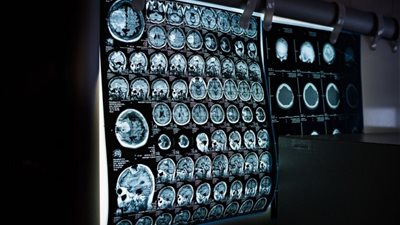

وتمكن الجراحون من إزالة الورم الضخم من رأس رابيندرا بيسوي، حيث خضع لإجراء عملية جراحية معقدة استمرت 10 ساعات، وعاش رابيندرا بيسوي مع الورم لمدة 25 عامًا، قبل أن يتمكن الجراحون من تخليصه منه، وخاصة أن ارتفع حجم النمو الصغير بسرعة في الأشهر الـ 7 التي سبقت العملية، ووصل إلى 15.43 رطلًا وأثر بشدة على حركته وعمله وتنفيذ أنشطته اليومية.

وأشار الجراحين من معهد عموم الهند للعلوم الطبية، إلى أن شكلت إزالة الورم تحديًا كبيرًا للجراحين، نظرًا لندرته وطبيعته العدوانية، كما أحاط الورم عدد من الأوعية الدموية، مما جعل العملية صعبة بشكل خاص.

وقال الدكتور سانجاي جيري، رئيس قسم الحروق والجراحة التجميلية في معهد عموم الهند للعلوم الطبية، بوبانسوار، الورم كان منتفخًا بشكل غير عادي، وإزالته من فروة الرأس كانت محفوفة بالمخاطر، ونظرًا لخطورة الجراحة، فقد تطلب الأمر فريقًا متعدد التخصصات من الأطباء، لإزالة الورم، وشارك أطباء جراحة الأعصاب والتخدير والأشعة التداخلية وجراحة الأورام، وخلال العملية الصعبة التي استغرقت 10 ساعات، بذل الجراحون قصارى جهدهم للتأكد من بقاء عظم جمجمة رابندرا سليمًا، وكانت العملية ناجحة وتمكن الجراحون من إزالة الورم بالكامل.